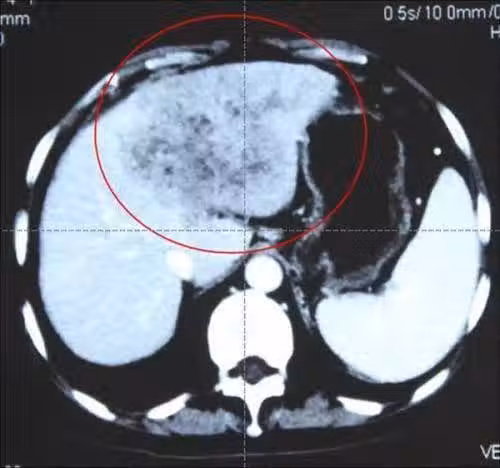

小強,今年28歲,目前還是單身,在工作單位附近租了個房子,自己獨自居住。 由於工作時間不固定,經常要加班,小強很喜歡吃海鮮,但是海鮮很難存活,於是買來的全部海鮮都做熟後放在冰箱中,吃的時候拿出來加熱一下。 並且小強平時還喜歡喝點酒,下酒菜常常就是加熱一些海鮮,再做一個涼拌木耳,因為木耳食用方法很簡便,水中泡幾分鐘,涼調一下就可以了。

於是小強一次就泡上一盆,放在冰箱裡,下了班抓一把調一下,就著白酒,吃點海鮮。 最近一段時間,小強常常感到右腹部疼痛,同時還伴有腹瀉,臉色是一天不如一天。 於是小強便來到醫院檢查,結果讓他怎麼也沒有想到,竟是查出肝癌ai期,由於並且嚴重,治療5個月後不幸離世。